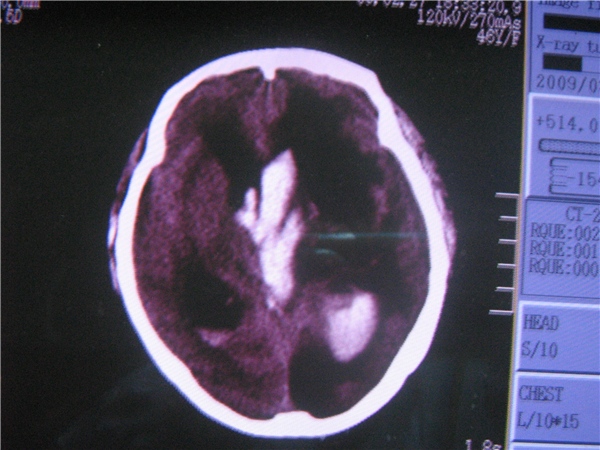

f 46y 有高血压病史。(ct-30991)

1)左侧丘脑出血破入脑室系统。2)脑积水。3)左侧额颞顶枕叶脑软化灶。

1双侧侧脑室,第三,四脑室区出血考虑丘脑出血破入脑室(没看清就要考虑,其实应该是丘脑出血的)

2左枕叶软化灶可能性大

3脑积水可能性大(不好意思我定不下来)

左侧丘脑出血破入脑室系统伴脑积水。